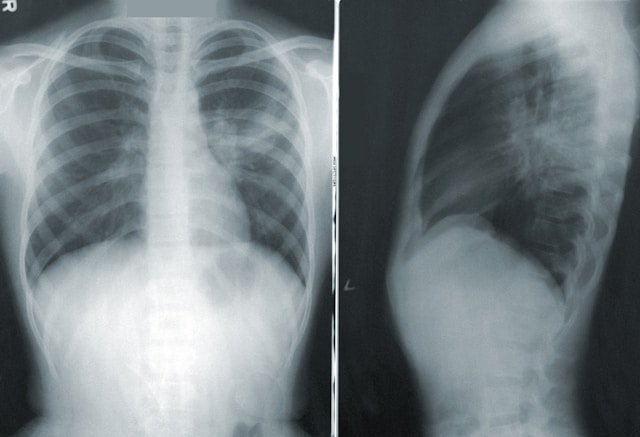

Sindh Government Qatar Hospital in Karachi has become the first healthcare facility in the province to introduce artificial intelligence (AI) for tuberculosis (TB) diagnosis. The cutting-edge Cat 4 Integrated AI X-ray machine, now installed at the hospital, can detect TB and other chest infections within just five minutes—revolutionising early detection and treatment.

Dr. Rashid Siraj Khanzada, the hospital’s Medical Superintendent, explained that the machine converts grayscale X-ray images into colour scans using AI. If TB or a chest infection is present, the affected areas turn red, allowing for an immediate diagnosis. Previously, TB detection could take days, during which an infected patient could unknowingly spread the disease to 15–20 others.